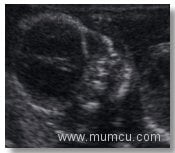

5 hafta 6 günlük gebelikte kalp atımlarının renkli doppler ile izlenmesi

Vajinal ultrasonografi